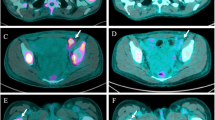

Flow cytometry analysis

For the apoptosis assay, cells were stained with Alexa Fluor 488 labelled Annexin-V and propidium iodide with an Alexa Fluor 488 Annexin-V/Dead Cell Apoptosis Kit (Thermo Fischer Scientific) for 15 min at room temperature in the dark. Stained cells were resuspended with the buffer in the kit.

For the mitochondrial depolarization assay, cells were stained with 1 μM of JC-1 dye (Thermo Fischer Scientific) for 30 min at 37 °C in 5% CO2. JC-1 stained cells were washed by resuspending with PBS and then. The mitochondrial depolarization rate was defined by green fluorescence in the surviving population as judged from the scatter plot.

For evaluation of the proportions of wild-type CD74-ROS1, F2004V- and F2075C-mutated cells in the presence 0 or 10 nM of cabozantinib, wild-type CD74-ROS1 cells were stained with PKH67 (green fluorescence) and F2004V- and F2075C-mutated cells were stained with PKH26 (red fluorescence, both from Sigma) according to the manufacturer’s instructions. Each population was defined by the corresponding fluorescence intensity in the surviving population as judged from the scatter plot.

Each sample was analysed by flow cytometry with Cytomics FC500 (Beckman Coulter). Output data were using FlowJo software ver. 7.6.5 (FlowJo, LLC).